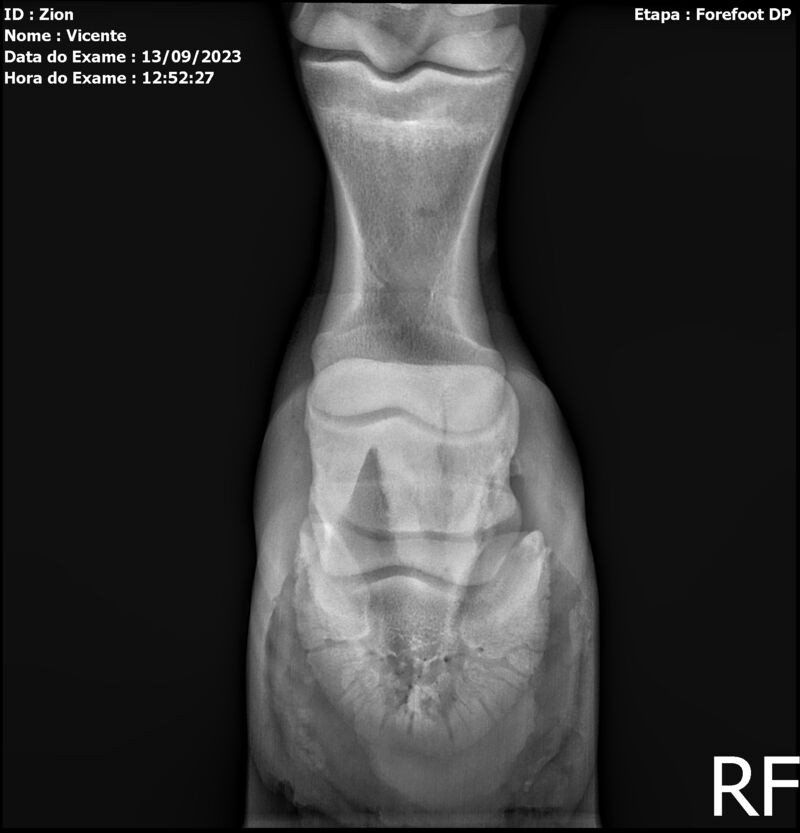

ZION ZC

Raça: BRASILEIRO DE HIPISMO

Sexo: MACHO - POTRO

Nascimento: 17/12/2022

Altura Aproximada: 1,51

Pel.: CASTANHO

Registro: EM AND

Vend.: VICENTE CONTE

Local : PORTO FELIZ/SP